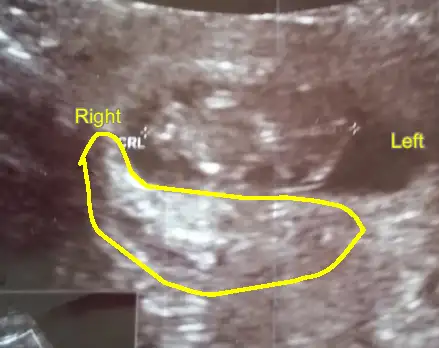

Aa ucretlimi ok tatlim rabbim gonlune gore nasip etsin insallahKizlar ben bu resmi yurtdisinda tahmin yapan bi siteye yolladim..ingilizce olarak geldi cevap.yalniz 5 $ucreti.plesentanin konumunu isaretlemisler.plesenta sag tarafta buyumeye baslamis yani usg de solda gorunuyor.erkek tahmin ediyolar.ama dr um 12. haftada kiza benziyor dedi.bakalim hangisi dogru..

12 + hafta usg resmi paylas orada nupa gore tahmin ediyorlar konu adi doktor soylemeden siz gorun genital nup teorisi (bebegin cinsiyetini)Kizlar ben bu resmi yurtdisinda tahmin yapan bi siteye yolladim..ingilizce olarak geldi cevap.yalniz 5 $ucreti.plesentanin konumunu isaretlemisler.plesenta sag tarafta buyumeye baslamis yani usg de solda gorunuyor.erkek tahmin ediyolar.ama dr um 12. haftada kiza benziyor dedi.bakalim hangisi dogru..